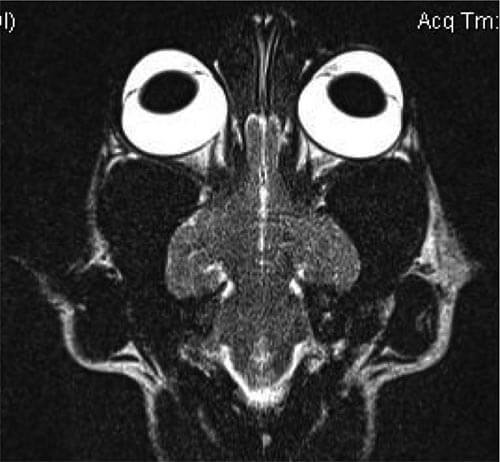

Inceputul dezvoltarii metodei de diagnostic imagistic prin Rezonanta Magnetica este corelat cu Premiul Nobel pentru Fizica din 1952 acordat savantilor Felix Bloch si Edward Purcell care au descoperit independent unul de altul fenomenul de rezonanta magnetica. Descoperirea lor a demonstrat o proprietate a nucleului atomic ce are un numar impar de nucleoni care se rotesc la o frecventa radio in jurul nucleului atomic intr-un camp magnetic, frecventa radio fiind dependenta de puterea campului magnetic.